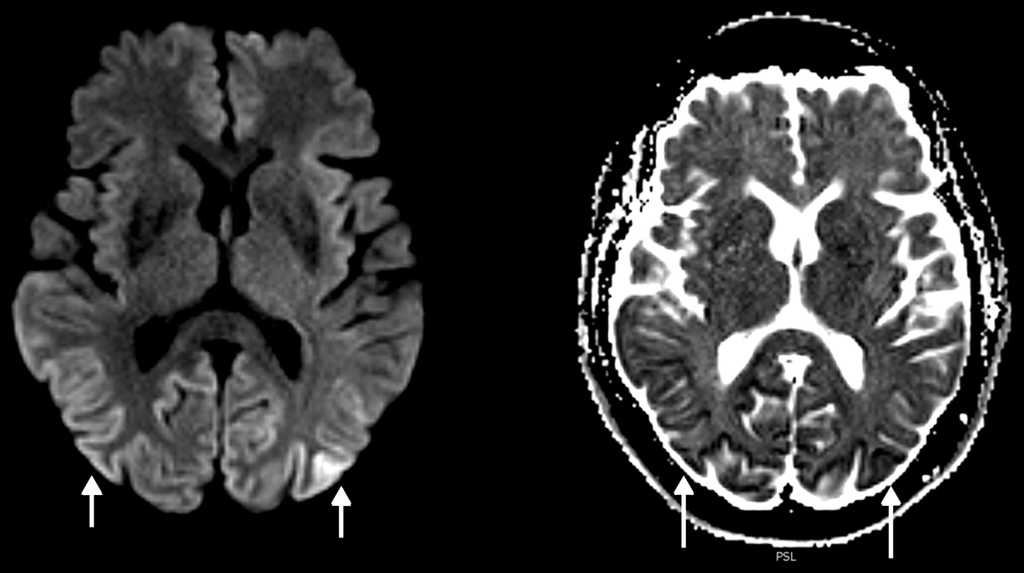

En una resonancia magnética (RM) cerebral hecha en un equipo de 3 Teslas (3 T), que se había realizado 6 semanas antes en otro centro, se observaba restricción a la difusión en la corteza parieto-occipital bilateral. Estos hallazgos fueron confirmados y superpuestos a la RM (3 T) realizada en nuestro centro al segundo día del ingreso (fig. 1). A los dos meses se llevó a cabo una RM de control con hallazgos similares, aunque menos evidentes, al ser hecha con un campo abierto de 1 T.

Los hallazgos de la RM puede ser uni o bilaterales y simétricos o asimétricos, e incluyen hiperintensidad en ponderación T2 y en atenuación del fluido en inversión-recuperación (FLAIR) de los ganglios basales (putamen y caudado), tálamo (signo del palo de hockey), corteza (manifestación temprana más común) o sustancia blanca4,5,7,8. En la ECJv los cambios se observan típicamente en el tálamo (signo del pulvinar). En la secuencia de difusión (DWI) es característica la difusión restringida persistente, especialmente evidente en los equipos de alto campo, siendo esta la secuencia más sensible para las alteraciones corticales, además de ser superior a las secuencias ponderadas en T2 y FLAIR en estadios tempranos2,7 (fig. 2). En la variante de Heidenhain son características las alteraciones de señal de los ganglios basales y típicamente del cortex occipital2,3. También se produce atrofia cerebral progresiva rápida.